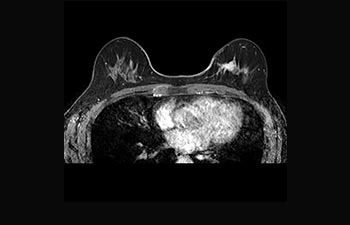

La Sra. Silvia Schiffer, directora y radióloga experta en la clínica Radiologie Schiffer, en Alemania, comparte sus experiencias con el sistema de RM Prodiva 1.5T.